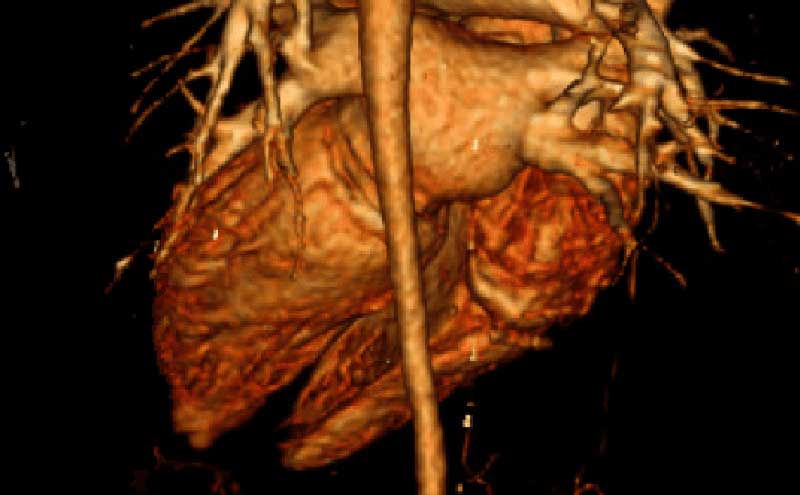

Patient underwent CT angiogram of her chest and abdomen emergently and the findings were suspicious for “periaortitis in association with midaortic syndrome with severe stenosis/near occlusion of the infrarenal aorta, bilateral renal arteries, celiac trunk, and SMA.” Findings that could represent a vasculitis versus neoplastic process.

Aorta computed tomography

Aorta narrowing on CT

Narrowing of aorta recon

Occluded aorta

Thickened aorta on CT